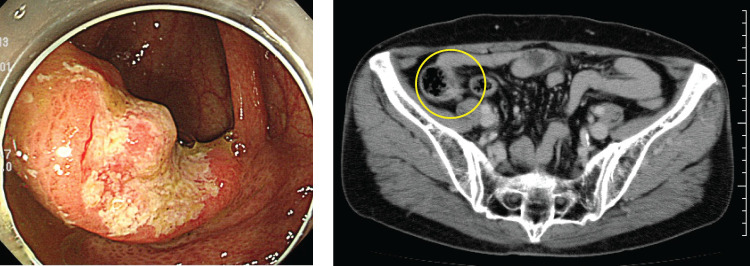

Case presentation: A 67-year-old woman underwent colonoscopy due to positive fecal occult blood. Biopsy revealed a 20-mm type 2 tumor in the ascending colon near the ileocecal valve, which was a poorly differentiated adenocarcinoma. She underwent laparoscopic-assisted ileocecal resection and D3 dissection, and the surgery was completed routinely in which functional end-to-end anastomosis (FEEA) was performed extracorporeally. Postoperative course was good and she was discharged one week postoperatively. The pathology showed AI, type 3, 30 × 23 mm, 40%, por2>sig>tub2, pT3a (SS), int, INFb, v2, ly3, Pn1b, PM1, DM0, pN1. There was widespread cancerous extension along the intermuscular plexus within the intrinsic muscular layer of the ileum, and although grossly separated from the tumor by about 80 mm, the tumor was R1 resected with positive oral margins. Additional anastomotic resection was performed by laparotomy. Intraoperatively, the resected section was submitted to a rapid examination, which was confirmed to be negative, and the surgery was completed. The pathological examination revealed that the resected specimen showed an adenocarcinoma on the ileum side of the anastomosis, which infiltrated and proliferated within the intermuscular plexus by about 15 mm, although the tumor was not visually recognized on the resection specimen. Both bilateral margins were negative, resulting in R0 resection. Postoperative adjuvant chemotherapy was not requested by the patient. Thereafter, periodic imaging follow-up was performed and, nine months after the initial diagnosis, there was no increase in tumor markers and no evidence of recurrence on imaging.